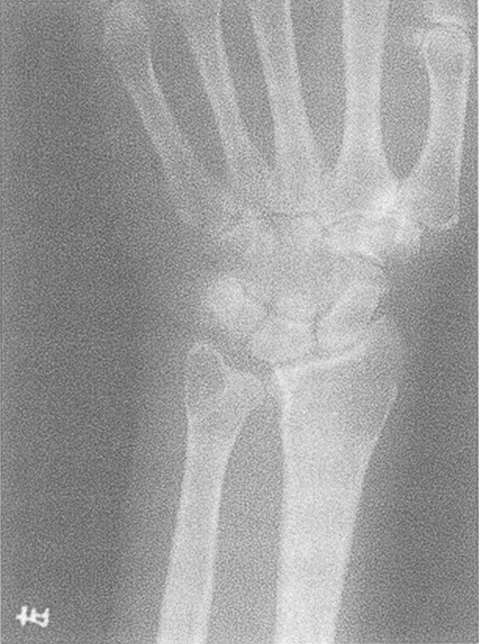

近關(guān)節(jié)骨囊腫好發(fā)于下肢骨,以股骨頭及頸最為多見,約占37%,其次為脛骨下端,再次為脛骨上端。約有23%的病例發(fā)生在上肢,多累及尺骨及腕骨近關(guān)節(jié)骨囊腫多位于骨骺,但亦可發(fā)生于干骺端。表現(xiàn)為圓形或卵圓形透亮區(qū),多偏心性發(fā)病,大小不等。囊腫為一種純?nèi)芄切?、無侵蝕性病變,多有一硬化邊緣,鄰近的關(guān)節(jié)造影偶能證實囊腫與關(guān)節(jié)相通。

微創(chuàng)激素聯(lián)合人工骨注射治療骨囊腫或動脈瘤樣骨囊腫北京大學(xué)第一醫(yī)院骨腫瘤科燕太強2024.2.16單純性骨囊腫或動脈瘤樣骨囊腫屬于臨床上比較常見的兒童良性溶骨性腫瘤,臨床經(jīng)常見到對這兩種腫瘤的過度處理?;純翰坏惺芰碎_放手術(shù),而且術(shù)后很容易復(fù)發(fā)。本篇科普不是討論這兩種病變的診斷和鑒別診斷,而是推薦采取微創(chuàng)治療的方法,不開刀,且可以達到治愈腫瘤的目的,與大家分享我們成功的經(jīng)驗。病例1女性,10歲,右肱骨近端單純性骨囊腫,病理性骨折(A),微創(chuàng)激素人工骨注射(B),1年后復(fù)查,病變修復(fù)(C)。病例2男性,7歲,右股骨近端單純性骨囊腫(A),疼痛,行走障礙,術(shù)中微創(chuàng)治療(B),術(shù)后1個月復(fù)查(C),術(shù)后1年復(fù)查,囊腫消失,病變修復(fù)良好(D),運動正常。病例3女性,9歲,右腓骨遠端單純性骨囊腫(A),疼痛,行走障礙。微創(chuàng)激素人工骨注射術(shù)后片(B),術(shù)后6個月復(fù)查(C),術(shù)后1年復(fù)查,囊腫縮小明顯,病變修復(fù)良好(D)?;颊咝凶哒!2±?女性,13歲,右髖臼動脈瘤樣骨囊腫(A),疼痛,跛行。微創(chuàng)激素人工骨注射術(shù)中(B),術(shù)后片,人工骨充填滿意(C)。術(shù)后每月注射一次地舒單抗,術(shù)后6個月復(fù)查,囊腫邊界硬化,病變修復(fù)良好(D)。患者行走正常。已改為地舒單抗3個月注射一次。病例54歲男孩,右股骨近端囊性病變(A),在當(dāng)?shù)匦泄纬补鞘中g(shù),術(shù)后病例為動脈瘤樣骨囊腫,術(shù)后半年復(fù)查植骨吸收,病變擴大(B)。在當(dāng)?shù)匦械诙喂纬补切g(shù),術(shù)后4個月,病變進一步擴大(C)。繼續(xù)觀察2個月,出現(xiàn)病理性骨折,無法行走(D),當(dāng)?shù)亟ㄗh再次手術(shù),家屬拒絕。在我院行微創(chuàng)激素人工骨注射術(shù)后片(E),術(shù)后給予地舒單抗60mg,每月皮下注射一次,六次后復(fù)查片(F),患兒行走正常(視頻附后)。改為3個月注射一次,1年后停用。復(fù)查X線片(G)?,F(xiàn)微創(chuàng)治療后已超過兩年,患者已恢復(fù)學(xué)校生活。